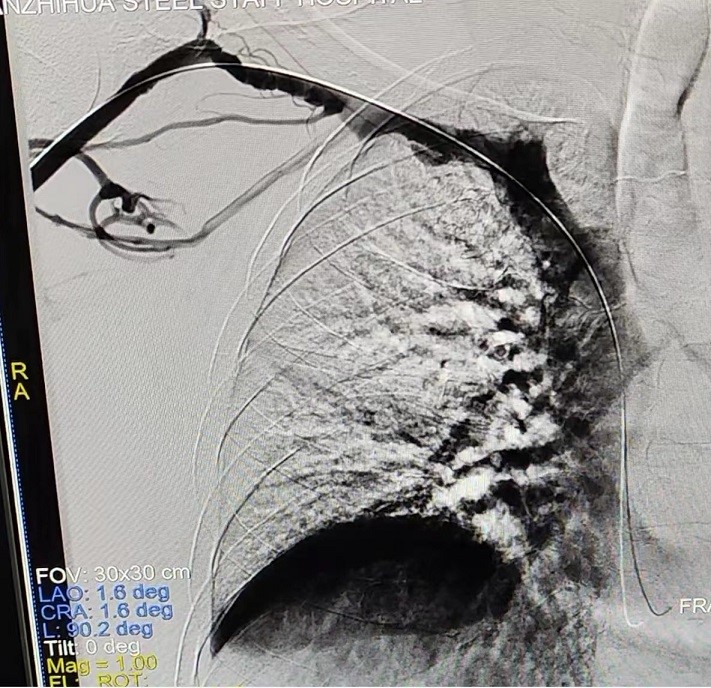

術后造影顯示:右鎖骨下靜脈狹窄完全打開

手術中,主刀醫(yī)生唐靜通過DSA順利對人工血管中形成的血栓進行了取栓。之后,在中心靜脈造影下,發(fā)現(xiàn)患者中心靜脈外周有2cm的狹窄,尤其是右鎖骨下靜脈得狹窄已經嚴重到幾乎閉塞,針眼大小的縫隙僅能容下導絲通過。經過反復嘗試與不懈努力,終于將導絲置入,并用12 *40mm的球囊擴張,右鎖骨下靜脈成功開通,患者透析的通道打開了。術后,家屬看著消腫的手臂感激萬分,眼淚奪眶而出。